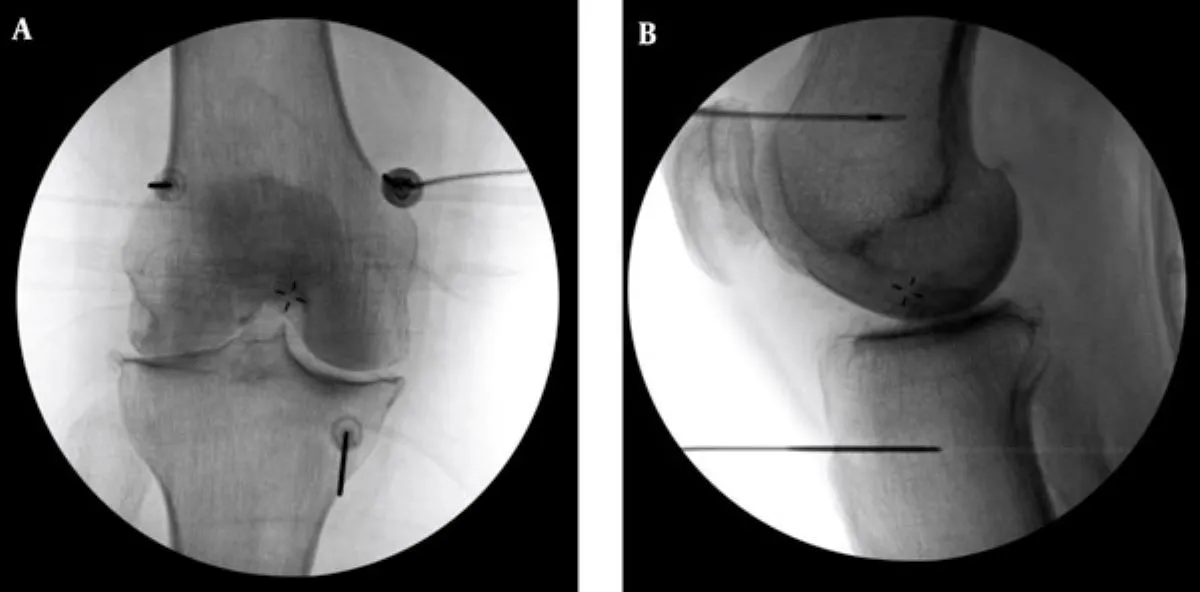

李宜轩说,若病情仍在中度前,通常可靠药物、复健、减重与肌力训练改善;但不适合手术者,可考虑「高频热凝疗法」。此疗法原本用于治疗下背痛与坐骨神经痛,现在也能精准止住膝关节痛。医师会在局部麻醉下,以X光定位导针至膝盖三个主要神经点,再输出电波热能,使痛觉神经暂时失去传导功能。效果通常在术后一周内出现,可维持半年至2年。

高频热凝疗法以X光定位将电极导针导引至膝盖的三个主要感觉神经丛,借由热能与电效应,麻痺痛觉神经。台北慈济提供